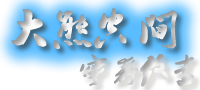

顾名思义,大量含有纤维结构的颗粒体类似于抛光后的白色大米,偶发于慢性滑膜炎症性关节,以游离或嵌入固定的形式存在于滑囊内。1895 年 Riese 首次于 1 例结核性膝关节炎病例中发现并报道。

我们采用三角肌胸大肌入路,进行切开清理 + 广泛滑膜清理术。